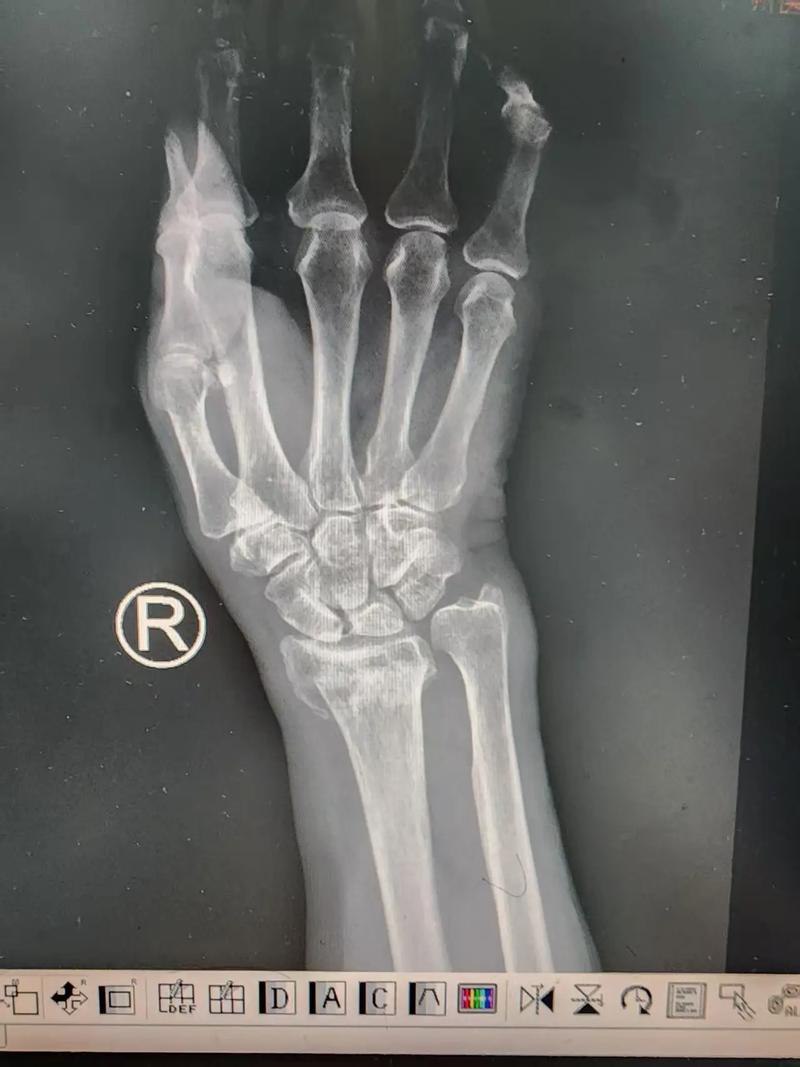

长沙一大二男生挑战掰手腕,手部粉碎性骨折!怎么回事?

其实因为掰手腕受伤的在临床并不少见,每年都能见到几个!但我本人见到的都是肱骨中下段骨折,至于手部粉碎性骨折至今还没见到[捂脸]!

因为掰手腕时,自身肌肉收缩以对抗外力带动前臂内旋!这时自身肌肉收缩力与外力形成的剪切力都作用于肱骨,而因为肱骨的解剖特性,其中下三分之一处结构最为薄弱!所以掰手腕导致的常常就是肱骨中下段的螺旋形骨折。

至于手部粉碎性骨折!我猜测最大的可能就是:1、对手握力太强,把患者手部骨骼捏碎;2、患者骨质太松(但对于一名大二学生可能性不大)。